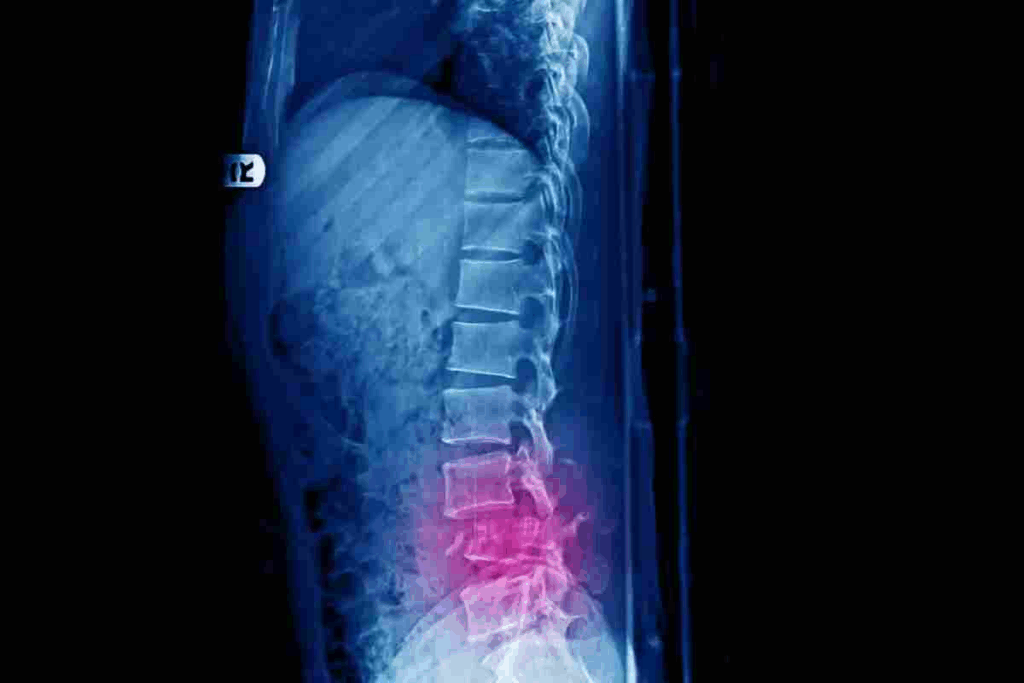

It’s important to know about L1 compression fractures to manage and treat them well. An L1 compression fracture happens when the L1 vertebra in the lumbar spine collapses or gets compressed.

A compression fracture is when a vertebra collapses, often because of osteoporosis or trauma. The L1 vertebra is key in the lumbar spine, supporting our body’s structure.

This collapse can cause chronic pain and deformity. Knowing about this injury is key to giving the right care.

Imaging tests are vital to confirm the diagnosis and see how bad the fracture is. We use X-rays, CT scans, and MRI to get a clear picture of the fracture.